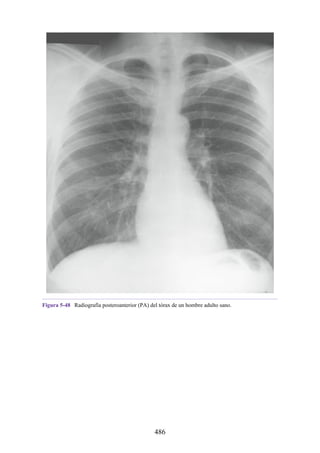

Notas clínicas

225